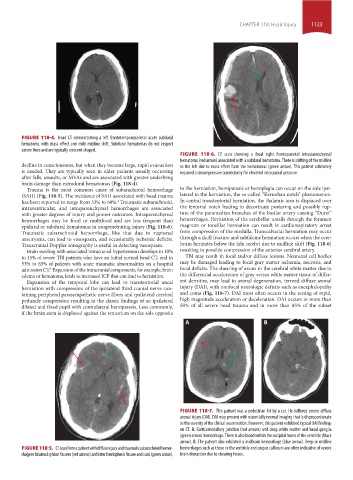

FIGURE 118-6. CT scan showing a focal right frontoparietal intraparenchymal

hematoma (red arrow) associated with a subdural hematoma. There is shifting of the midline

decline in consciousness, but when they become large, rapid evacuation to the left due to mass effect from the hematomas (green arrow). This patient ultimately

is needed. They are typically seen in older patients usually occurring required a decompressive craniectomy for elevated intracranial pressure.

epidural or subdural hematomas in nonpenetrating injury (Fig. 118-6). magnum or tonsillar herniation can result in cardiorespiratory arrest

Transcranial Doppler sonography is useful in detecting vasospasm. brum herniates below the falx cerebri due to midline shift (Fig. 118-6)